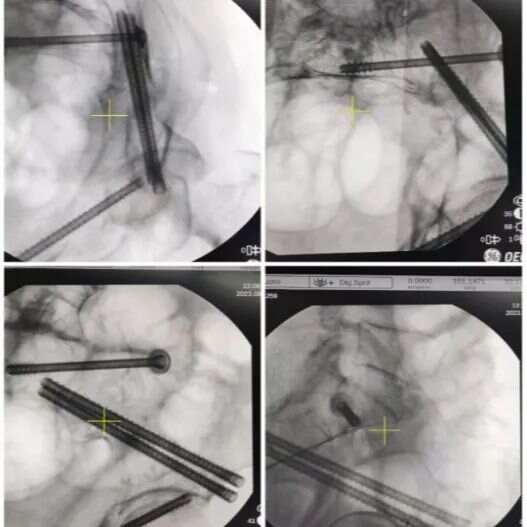

△術(shù)中影像及手術(shù)切口

通道螺釘手術(shù)就是用幾根長(zhǎng)度不同的螺釘將復(fù)位后的骨盆骨折穩(wěn)定固定,由于骨盆周?chē)笱芗吧窠?jīng)密布,失之毫厘差之千里。創(chuàng)傷骨科醫(yī)療組謹(jǐn)慎嚴(yán)密地完成了術(shù)前設(shè)計(jì),結(jié)合3D打印技術(shù),設(shè)計(jì)通道螺釘?shù)倪M(jìn)釘點(diǎn)及螺釘?shù)耐ǖ婪较?、長(zhǎng)度,術(shù)中通過(guò)骨盆入口位、出口位、骶骨側(cè)位、髂骨斜位、閉孔斜位等多角度術(shù)中XC臂機(jī)透視,精準(zhǔn)植入通道螺釘,避免了術(shù)中損傷環(huán)骨盆血管、神經(jīng)及螺釘穿出關(guān)節(jié)。

蔣大爺疼痛緩解明顯,術(shù)后第一天即可在床上坐起,蔣大爺告訴醫(yī)生:“我的疼痛明顯減輕,雙腿也可以開(kāi)始活動(dòng)了,不用躺在床上幾個(gè)月,而且花費(fèi)少,真是太好了!”